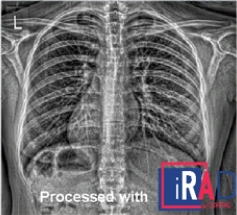

Veja a diferença que nossa tecnologia faz nas imagens médicas

O iRAD aprimora imagens de raio-X revelando características difíceis de ver, melhorando contraste, nitidez e realce de bordas, proporcionando diagnósticos mais precisos com menor exposição à radiação.

Processado com iRAD

Original

Processado com iRAD